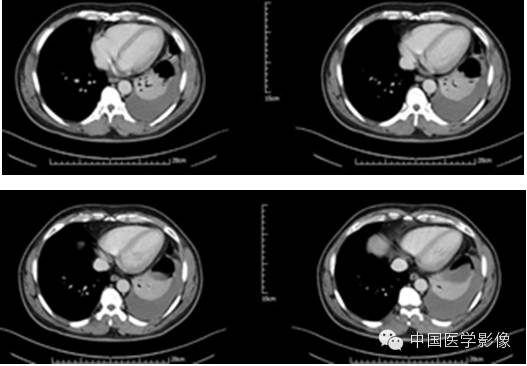

病例2【病史】

患者男,47岁。

患者因“查体发现右纵膈区占位2周”入院。患者无胸痛、胸闷,无发热、盗汗,无咳嗽、咳痰。CT示:右心膈角处新生物,考虑来自叶间裂的炎性假瘤可能性大,不除外其他肿瘤可能。

专科查体:(-)

入院诊断:右下纵膈占位:心包囊肿?炎性假瘤?

【影像资料】

平扫

动脉期

静脉期

延迟期

【病理结果】

孤立性纤维性肿瘤